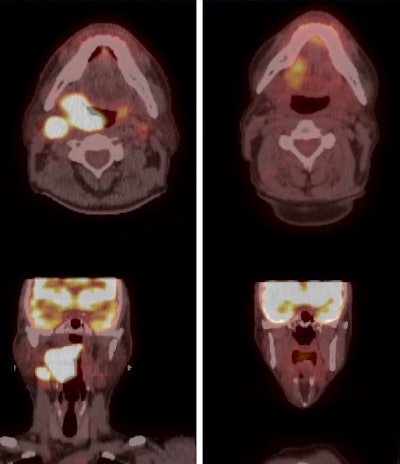

PET/CT images illustrate a patient's initial staging and treatment planning (left column) and the response to three months of radiation therapy (right column). Image courtesy of Dr. Jessica Frakes.Most importantly, the three-year overall survival rate was 91%. There were 19 cases of grade 3 toxicities, and two patients had grade 4 toxicities.